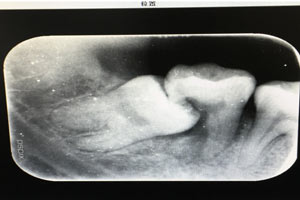

患者、申xx、女、40歲,主訴:左側(cè)下頜后牙牙齦紅腫不適數(shù)月。??茩z查:37合面有一開(kāi)髓孔。髓腔內(nèi)有一暫封小棉球,探針?biāo)枨坏撞砍鲅蔀樵谕庠褐委煂?dǎo)致底穿。x線片檢查:37頰側(cè)齦下有一枚多生牙,多生牙壓迫頰側(cè)牙根及牙體組織大量吸收。

圖1.術(shù)前的CBCT檢查:37頰側(cè)部分牙根被完全壓迫吸收。